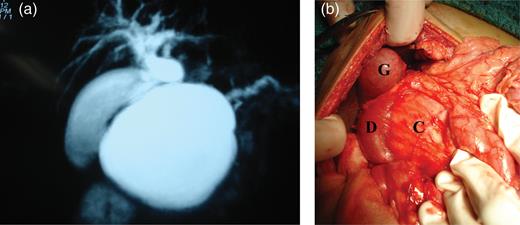

(a) MRCP with 2D-reconstruction demonstrating features indicating a type 1 choledochal cyst, (b) intra-operative showing gallbladder (G), duodenum (D) stretched and compressed with widened C loop of duodenum and the pseudocyst (C) within.

The patient was operated and the intra-operative findings (Fig. 1b) were of a large pseudocyst of pancreas arising predominantly from the head and body of the pancreas. The ‘C loop’ of the duodenum was splayed and stomach was pushed up anteriorly. Gall bladder and the portal anatomy were normal. The liver was enlarged and surface had fine nodules. There was no sign of active pancreatitis. An intra-operative cholecystogram was performed that showed unequivocal obstruction of the terminal common bile duct (CBD).